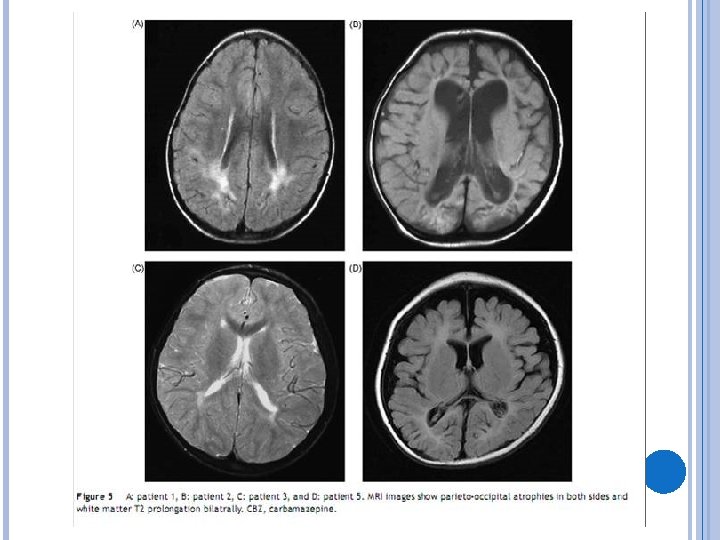

RESULTADOS Características das convulsões epilépticas e curso clínico da epilepsia (tabela 3) -o início da epilepsia variou entre 10 meses a 3 anos Todos os pacientes apresentaram status epilepticus EEG e Ressonância magnética (tabela 4; figuras 3 a 5) EEGs interictais mostraram picos occipitais ou parietooccipitais em todos os pacientes durante a infância

DISCUSSÃO - Sabe-se que a lesão cerebral induzida pela hipoglicemia predomina no lobo occipital. - Cinco dos pacientes do estudo tinham alterações na RNM, sendo 4 na região do lobo occipital, além de clínica de epilepsia do lobo occipital: isto sugere que a hipoglicemia neonatal possa ser a causa da epilepsia. - A encefalopatia hipóxico-isquêmica também predomina no lobo occipital; por vezes é difícil distinguir se a lesão cerebral decorreu da hipoglicemia ou da lesão hipóxico-isquêmica.